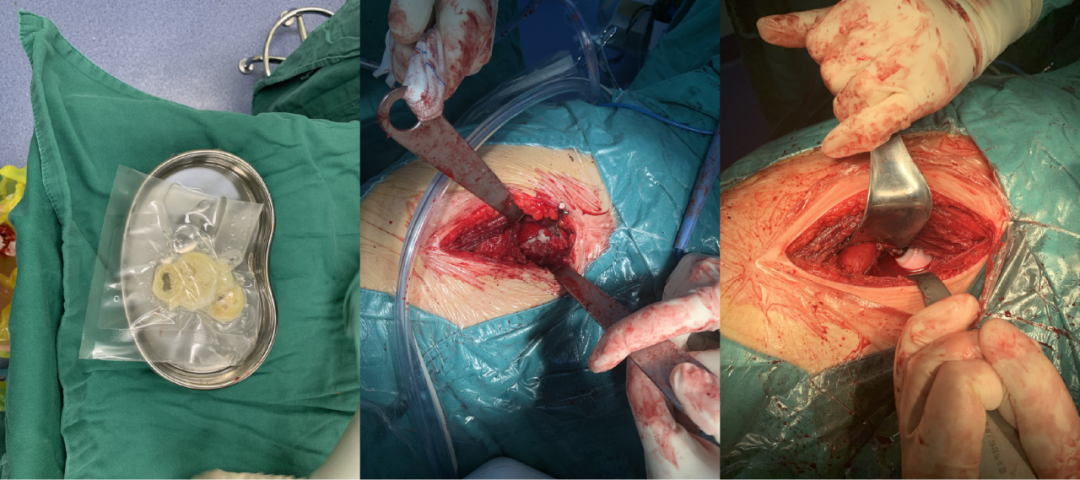

髋关节置换手术中收集自体骨组织

手术顺利,植入精准

临床骨缺损重建过程